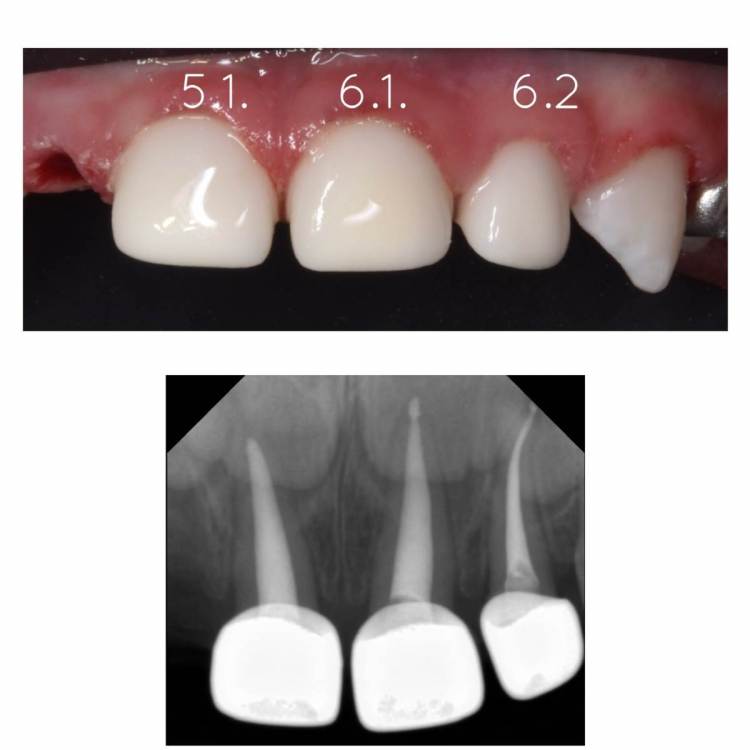

CRAZYDUCK Опубликовано 24 июня, 2022 Автор Поделиться Опубликовано 24 июня, 2022 Восстановление временных Резцов стандартными коронками . 3 1 Ссылка на комментарий

CRAZYDUCK Опубликовано 26 июня, 2022 Автор Поделиться Опубликовано 26 июня, 2022 Гипоминерализация . Границы препарирования … Будет ли разрушаться изменённая в цвете эмаль ? Этот вопрос остаётся открытым . Все , что жду от родителей - настаивать на гигиене и контролировать ее у своих детей и не забывать про регулярные осмотры . 3 1 Ссылка на комментарий